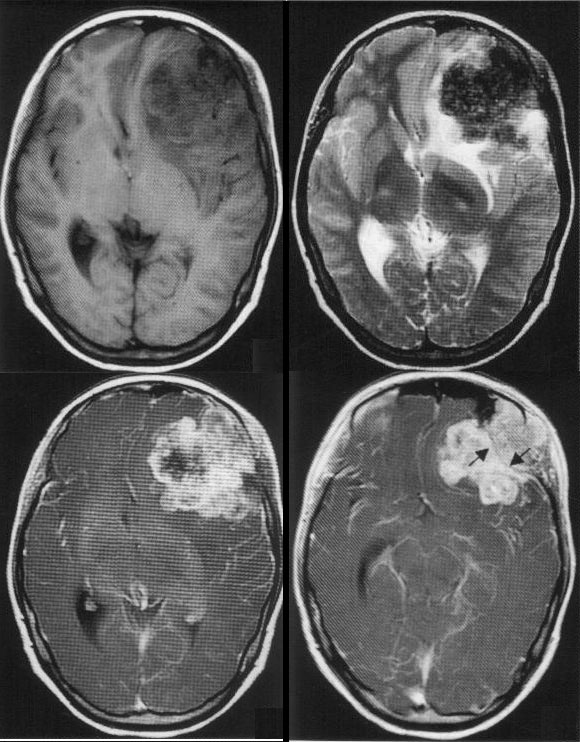

女,16岁。因反复头痛5个月,癫痫发作1次,并发现左侧额部一肿块突出1个月就诊。

这是一个罕见的恶性间叶肿瘤,主要由软骨肉瘤,平滑肌肉瘤构成,所以诊断起来难度较大。大体病理为额骨外侧眶板一菜花样肿瘤,大小约2.5 cm×2.0 cm,质硬,边界不清。此处硬脑膜未破。剪开硬膜后,额颞交界见裸露菜花样肿瘤,直径约5cm。边界清,将肿瘤全部游离切除,见左侧脑室颞角外侧壁完整,脑搏动正常,无肿瘤残余。不过由于我们前些日子刚刚分析过一例肝脏平滑肌瘤,如果考虑到那一例病变,也许会对本里有所帮助。

颅内原发性平滑肌肉瘤极为罕见,属于脑膜间质,非脑膜上皮细胞肿瘤,为新增的一类肿瘤。其诊断主要靠免疫组织化学,sm-actin表达均为阳性。影像学表现:常呈较大软组织肿块,边界大多清楚.部分呈浸润生长者,边界不清,其内mri信号不均,多有囊变、坏死,偶有出血、钙化;增强后常可有边缘性环状强化。本例病变平滑肌肉瘤部分与正常脑组织分界亦较清楚,边缘仅有轻度水肿,肿瘤信号不均,增强后呈明显不均匀强化,内可见片状无强化区。考虑为肿瘤坏死所致。

原发于颅内间叶性软骨肉瘤亦相当少见,是一种缓慢生长的局部侵犯性肿瘤,好发于颅底,易于压迫和侵犯穿行于颅底的颅神经。颅骨软骨肉瘤生长缓慢,初期症状不明显,故体积常较大,主要向颅内生长,可压迫、推移或浸润邻近脑结构,mr t1wi上呈低、等信号;透明软骨型t2wi上为高信号,但如果含有较多的矿物质则为低信号,无论那种软骨肿瘤中央常为低信号,增强后肿瘤呈不均一强化,较一般脑内实质性肿瘤强化显著。本例中软骨肉瘤部分亦位于前颅窝底,t1wi呈等低混杂信号,t2 wi亦呈低信号,增强后呈中度不均匀强化。

颅内原发性平滑肌肉瘤及原发软骨肉瘤均为罕见肿瘤,需要鉴别的有恶性脑膜瘤,恶性脑膜瘤亦表现为信号不均匀、不均匀强化、囊变、坏死、肿瘤外形不规则,但常有明显的瘤周水肿。另外需要注意的是,仔细观察在个别层面可以看到两种不同成分肿瘤间有一线样低信号分隔,及分隔线内外强化模式不同,此时也应想到两种肿瘤共存的可能性。与多数脑膜来源的恶性肿瘤一样,虽然mr检查特征性改变较少,但可以确定肿瘤的发病部位、大小、范围、生长方式、与周围结构的关系,对确定肿瘤的良恶性,以及有无远处转移、局部浸润等很有价值,对肿瘤治疗方案的制定亦有一定的指导意义。